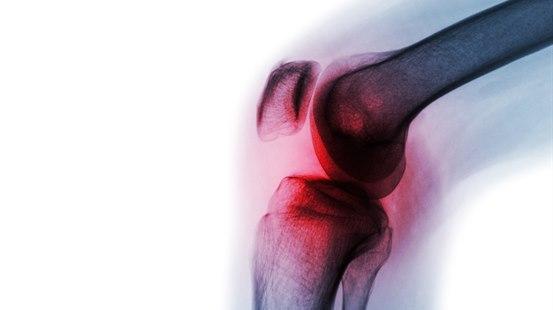

Ved artrose skjer en gradvis endring der mengden brusk reduseres og i enkelte tilfeller forsvinner helt. Det fører til betennelse (inflammasjon) i leddet og forandringer i knokkelen under brusken. Vanligvis gir det symptomer i form av smerte og redusert bevegelighet i leddene. Andre strukturer, slik som menisken i kneleddet eller musklene rundt et ledd, kan også bli svakere i denne prosessen.

- Kneleddsartrose kan gi stivhet, smerte og hevelse i kneet.

Artrose kan være synlig på vanlig røntgen av leddet, men ikke alle har forandringer på røntgen på tidspunktet symptomene debuterer. Det er sett at personer med større artroseforandringer på røntgen kan ha lette symptomer eller ingen symptomer i det hele tatt, mens personer med lite eller ingen artrose på røntgenbildet kan ha mye symptomer. Røntgen av leddet har derfor begrenset verdi og er ikke nødvendig for å stille diagnosen. Røntgen tas gjerne i forbindelse med planlegging av en operasjon eller når det er mistanke om at annen tilstand eller sykdom kan være årsak til plagene.